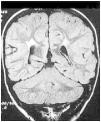

El origen es prenatal en más del 75% de los casos, y está relacionada con atrofia o lesiones porencefálicas en el territorio de la arteria cerebral media (fig. 2), o bien con displasias corticales.

Fig. 2. Resonancia magnética nuclear (RNM) cerebral potenciada en T2. Lesión extensa en el territorio de la arteria cerebral media derecha en paciente con hemiplejía congénita izquierda.